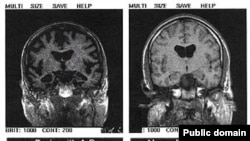

Два томографических снимка мозга. Справа - нормальный мозг, слева - пораженный болезнью Альцгеймера